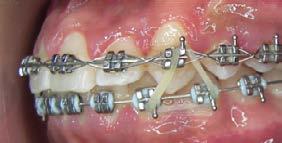

Adherencia a las indicaciones del tratamiento ortodóntico en pacientes con aparatología fija

La adherencia al tratamiento se define como el grado de comportamiento de una persona para seguir las recomendaciones sugeridas por el prestador de servicios de salud, en este caso, el ortodoncista. La adolescencia se considera una etapa idónea para recibir tratamiento de ortodoncia, ya que durante este periodo se presentan cambios fisiológicos, estructurales y anatómicos relacionados con el crecimiento y desarrollo de la cara y de las arcadas dentarias; sin embargo, uno de los principales retos es lograr y mantener una adecuada conexión con el paciente para obtener resultados favorables en la mejora de su oclusión. Objetivo: Evaluar el nivel de adherencia al tratamiento con aparatología fija en pacientes adolescentes del Instituto Bioprogresivo de Ortodoncia. Metodología: Estudio transversal con muestreo por conveniencia. Se evaluó el nivel de adherencia al tratamiento en pacientes atendidos en el Instituto mediante un cuestionario validado de autorreporte, aplicado durante los meses de agosto a diciembre de 2024. Se realizó un análisis descriptivo de la muestra y posteriormente se evaluó la frecuencia de reporte de los ítems. Resultados: El 81.7% de la muestra reportó haber recibido indicaciones higiénicas; el 85.3% recordó las instrucciones dietéticas recibidas; el 96.4% acudió a sus citas en la fecha y hora convenidas; el 97.5% refirió dar seguimiento a su tratamiento, aun cuando ya se sentían satisfechos con los resultados; el 92.6% solicitó consulta inmediata cuando se desprendió algún bracket; el 96.4% siguió las indicaciones incluso al salir de viaje; el 91.5% consultó oportunamente al ortodoncista ante la presencia de alguna molestia; el 92.6% recordó las fechas de sus próximas consultas, y solo el 2.5% reportó haber tenido conflictos con su ortodoncista. Conclusión: La adherencia de los pacientes al tratamiento de ortodoncia en la muestra fue adecuada; no obstante, es importante evaluar de forma constante este aspecto para verificar la motivación del paciente adolescente, evitar la deserción prematura del tratamiento y prevenir posibles complicaciones.

Palabras clave: adherencia, adolescentes, indicaciones, ortodoncia.

Las maloclusiones son consideradas un importante problema de salud pública. De acuerdo con la Organización Mundial de la Salud (OMS), estas constituyen el tercer problema de salud bucal más relevante, después de la caries dental y las enfermedades periodontales.1 Se estima que, en México, alrededor del 60% de la población presenta alguna de estas condiciones.2 Las maloclusiones son alteraciones en la posición de los componentes dentales o esqueletales del sistema estomatognático.3 Su efecto no es solo funcional y/o estético, sino que también influye en los aspectos psicosociales y en la calidad de vida de quienes las padecen.4

De acuerdo con la OMS, la adolescencia es el periodo comprendido entre los 10 y 19 años; en esta etapa se producen cambios físicos, psicológicos, biológicos, intelectuales y sociales que corresponden a la transición de la infancia al estado adulto.5 El abordaje de las maloclusiones se lleva a cabo mediante el tratamiento ortodóntico, en el cual se emplean distintos aditamentos con la finalidad de armonizar la oclusión y los rasgos faciales del tercio medio e inferior del rostro.6 La adolescencia es el momento preferido para realizar este tratamiento, ya que durante esta etapa la dentición permanente ha erupcionado, pero el crecimiento craneofacial aún puede aprovecharse.7

Para que el tratamiento ortodóntico sea exitoso, se requiere la cooperación del paciente en factores tales

como asistir a las citas, mantener una adecuada higiene oral, seguir las recomendaciones dietéticas, así como usar y cuidar los aparatos y aditamentos prescritos.8 Sin embargo, el tratamiento puede alterar las rutinas establecidas e interferir con las actividades sociales del paciente adolescente, además de repercutir en su autoestima debido a su aspecto físico. Por ello, resulta imperativo mantener una comunicación adecuada que permita comprender las necesidades y expectativas del paciente respecto al tratamiento y generar en este una adherencia adecuada a las indicaciones prescritas por parte del ortodoncista, a fin de favorecer el éxito del tratamiento.9

Resultados

Descripción de la muestra

En el estudio participaron 82 adolescentes; el 60.9% (n = 50) fueron mujeres, quienes presentaron una edad promedio de 15.3 ± 2.5 años. El 78.1% (n = 64) refirió que era la primera vez que se encontraba bajo tratamiento ortodóntico.

Adherencia al tratamiento

De acuerdo con la encuesta de adherencia en pacientes adolescentes bajo tratamiento ortodóntico, el 81.7% de la muestra reportó haber recibido

indicaciones higiénicas; el 85.3% recordó las instrucciones dietéticas recibidas; el 96.4% acudió a sus citas en la fecha y hora convenidas; el 97.5% refirió dar seguimiento a su tratamiento, aun cuando ya se sentían satisfechos con los resultados; el 92.6% solicitó consulta inmediata cuando se desprendió algún bracket; el 96.4% siguió las indicaciones incluso cuando salieron de viaje; el 91.5% consultó de manera oportuna al ortodoncista ante la presencia de alguna molestia; el 92.6% recordó las fechas de sus próximas consultas y solo el 2.5% reportó haber tenido conflictos con su ortodoncista (Tabla 2).